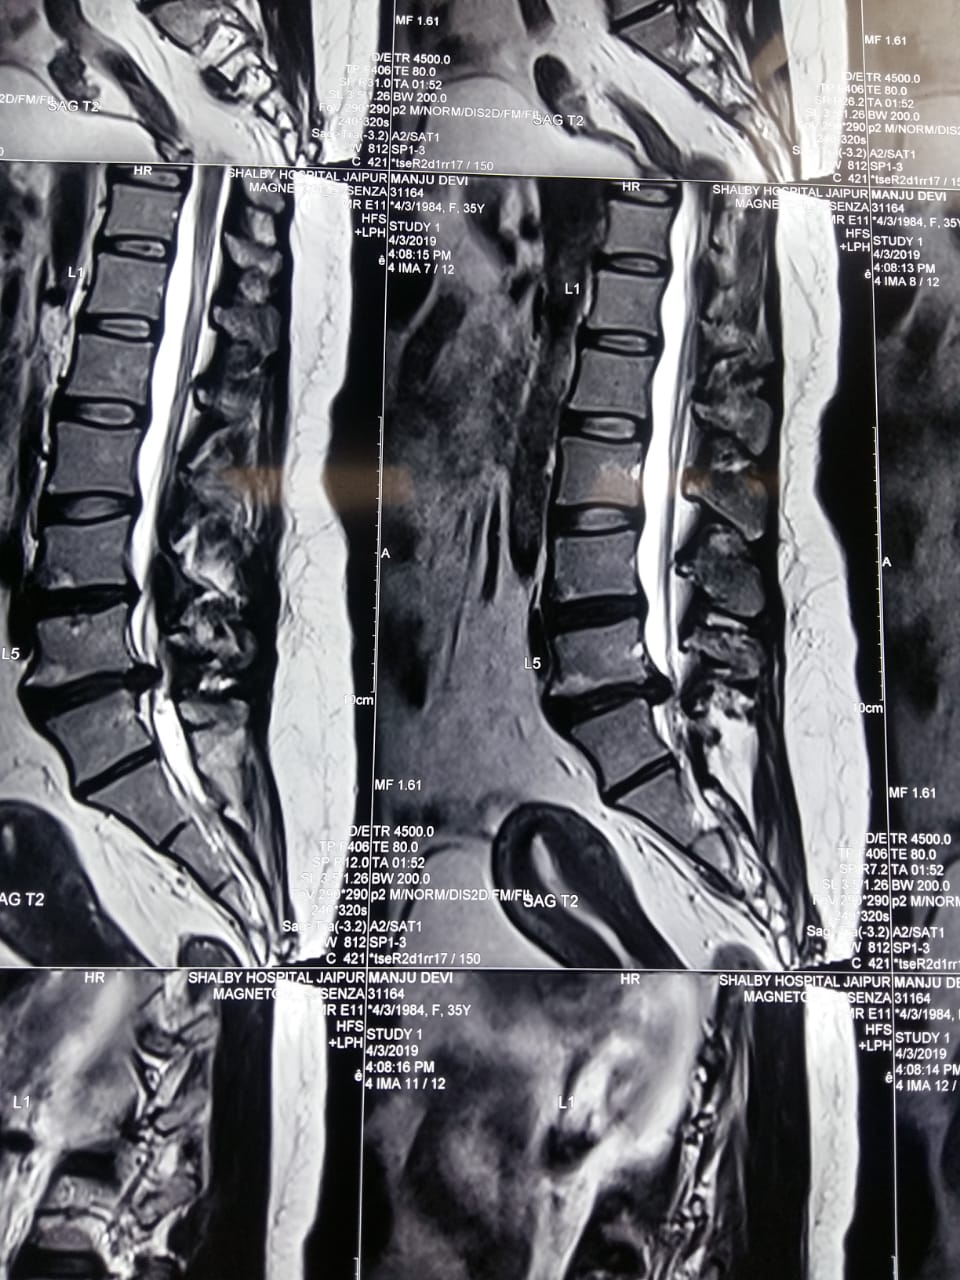

Big L5 S1 disc causing severe pain in left leg

MRI Showing slip disc